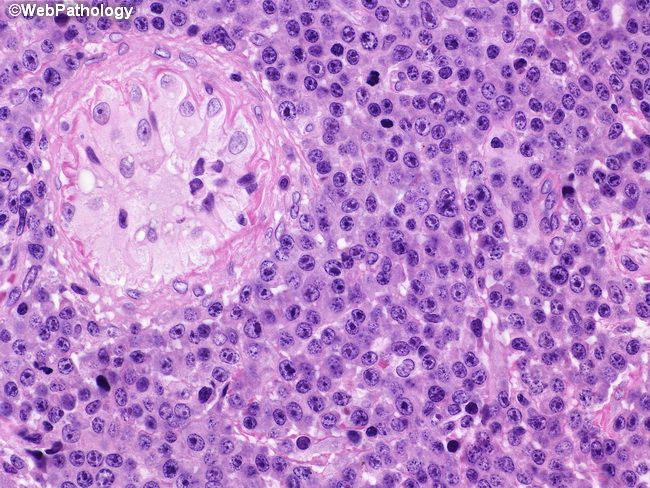

Плазмоцитома лечение

Плазмоцитома лечение 118 фотографий